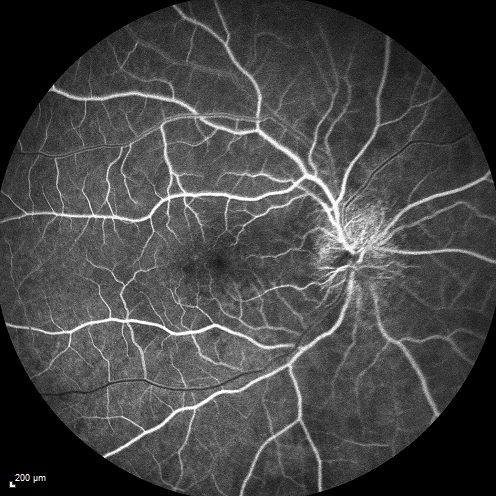

Syphillitic Optic Neuropathy and Maculopathy

46 year old woman with 2 weeks of vision loss OD.  VA 20/200 OD; 20/20 OS.  there are posterior vitreous cells on OCT in both eyes.  ICG, FAF, and FA show an abnormal macula OD.  VA improved to 20/30 within a month with treatment with PCN.